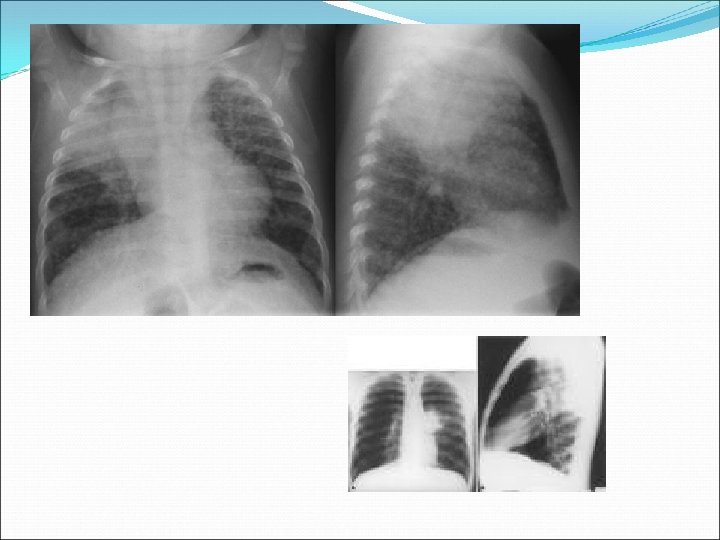

Endothoracic Pulmonary 1 ary pulmonary complex Adenopathy large w/ small parenchymal foci CXR hilar adenopathy, localized hyperaeration, atelectasis localized pleural effusion segmental infiltrate (foci) Signs/symptoms infrequent (except in infants) 1 ary complex: fever + cough Fever, cough, night sweats, FTT Localized wheeze, diminished BS Dysphagia, edema hand/arm

Hilar Adenopathy

Meron CXR 2 views Alert radiologist you are looking for TB